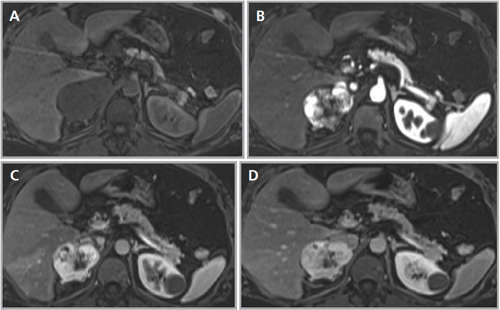

En la TC no contrastada las glándulas suprarrenales normales son homogéneas y simétricas, con una densidad muy similar a la del parénquima renal adyacente (Figura 1 a). Con un medio de contraste ev la glándula suprarrenal se opacifica en forma homogénea, similar al hígado o al bazo (Figura 1 b). Si la cantidad de tejido adiposo retroperitoneal es abundante las glándulas suprarrenales pueden aparecer enteramente rodeadas por grasa y su delimitación es más fácil (Figura 2 a); lo inverso ocurre en pacientes muy delgados con escasa grasa retroperitoneal (Figura 2 b). En RM, en secuencias ponderadas en T1 y T2 convencionales tienen una intensidad de señal homogénea, hipointensa respecto de la grasa adyacente e iso o hipointensa con respecto del parénquima hepático (Figura 3 a y b). En los cortes coronales se aprecia mejor la forma y la posición de las glándulas suprarrenales (Figura 3 c).

Figura 3. Glándula suprarrenal normal en resonancia magnética. (a) Cortes axial ponderado en T1 la señal de la glándula normal (flecha negra) es hipointensa respecto a la grasa retroperitoneal e isointensa respecto al parénquima hepático. (b) Cortes axial ponderado en T2 en que se muestra la glándula suprarrenal derecha (flecha blanca) y (c) corte coronal ponderado en T2 en que se muestra la glándula suprarrenal derecha (flecha blanca) y la glándula suprarrenal izquierda (flecha negra) con similares características de intendidad de señal. 3. Causas y prevalencia de las lesiones suprarrenales